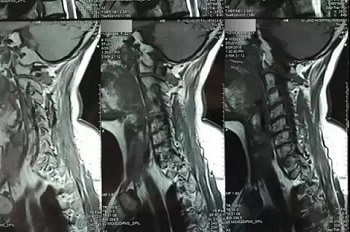

十一、将分区的磁共振图像,按顺序进行拍摄,即可获取如下比较有价值的清晰图片

十二、拍摄时,尽可能的将片子上的文字信息拍摄清楚,并将左右拍摄清楚(片子上有标R,表示右侧right,L, 表示左侧left的意思), 每张片子上的文字都能按照阅读习惯拍正确,不要拍反了。

拍摄时,必须要对着片子上的文字对焦, 方向正确,将文字拍摄得清晰可视,保证放大图片后文字依然清晰可见(如下图),尽可能多的保留片子上的信息。